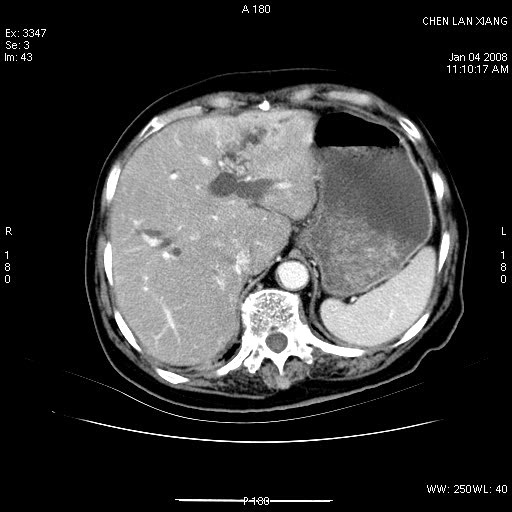

女,76岁,腹痛3-4天,b超示:肝内实性肿物,胆囊强回声,胆总管扩张.

考虑:1、胆总管下端结石伴梗阻性肝内外胆管扩张(肝左叶外侧段肝内胆管多发结石、胆管炎);

2、肿囊癌累及肝,不除外 黄色肉芽肿性胆囊炎。

1 胆总管末端结石伴肝内胆管结石,肝内外胆管扩张。2 胆囊扩大,胆囊壁不规则增厚,内见软组织密度影。考虑:慢性胆囊炎,不除外胆囊癌!

标题: 肝右叶病灶

胆囊癌侵犯肝右叶?

1)胆囊癌伴肝脏转移。2)胆总管下端结石、肝内胆管结石伴肝内外胆管扩张。